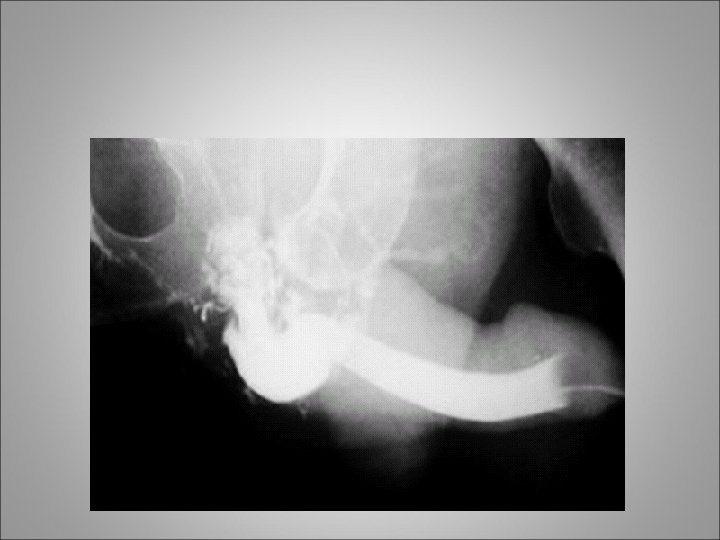

URETHRAL INJURIES • Classified into 2 broad categories based on the anatomical site of the trauma • Mechanism of injury include: blunt trauma such as MVA or falls, penetrating injuries, straddle injuries and Iatrogenic injury like traumatic catheter placement • Posterior urethral injuries commonly associated with pelvic fractures • Anterior urethral injuries come from blunt trauma to the perineum (straddle injuries)

URETHRAL INJURIES • Radiographic or cystoscopic evaluations to rule out this injury are mandatory in the following circumstances: • (1) when the patient presents with the classic triad of findings of a perineal/penile hematoma, blood at the meatus/vaginal introitus, and inability to void • 2) when one or more pubic rami are fractured or symphyseal diastases are present • (3) when radiographic findings suggest a bladder neck injury

Diagnosis • Symptoms include hematuria or inability to void • Physical examination may reveal blood at the meatus or a high-riding prostate gland upon rectal examination. Extravasation of blood along the fascial planes of the perineum is another indication of injury to the urethra • The diagnosis is made by performance of a retrograde urethrogram • "Pie in the sky" findings revealed by cystogram usually indicate urethral disruption

Management • The traditional intervention for patients with posterior urethral injury secondary to pelvic fracture is placement of a suprapubic catheter for bladder drainage and subsequent delayed repair • The suprapubic catheter can be safely placed either percutaneously or via an open approach with a small incision • Ultimate repair can be performed 6 -12 weeks after the event, after the pelvic hematoma has resolved and the patient's orthopedic injuries have stabilized

Management • An attempt at primary realignment of the distraction with a urethral catheter is reasonable in stable patients either acutely or within several days of injury (ie, 5 -7 d post injury) • When the urethral catheter is removed after 4 to 6 weeks, it is imperative to retain a suprapubic catheter because most patients will, despite realignment, develop posterior urethral stenosis